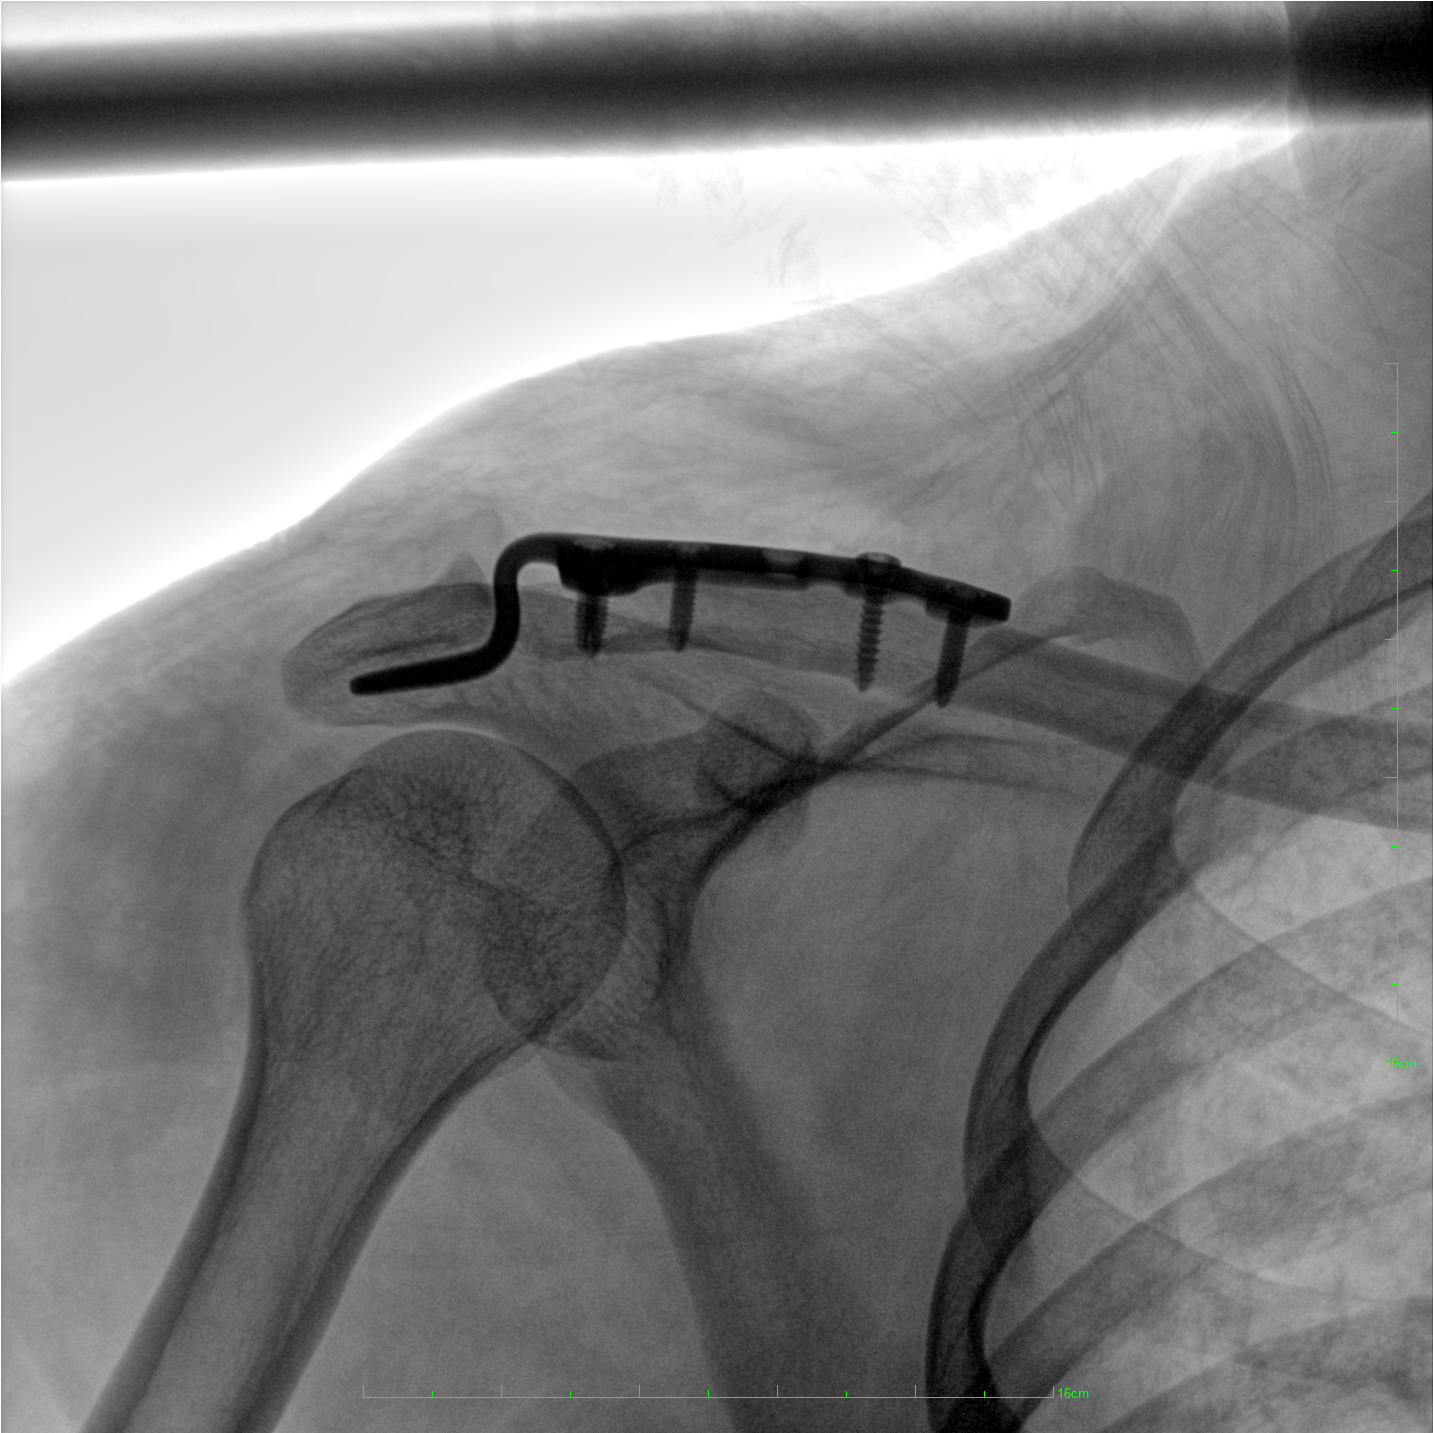

術中三維成像和橫斷面圖像提供多角度的手術診斷信息,輔助醫生進行術中評估判斷,諸如骨折復位情況和內植入螺釘的尺寸和位置,輔助手術更好地完成。

提供更大的術中三維成像視野,采集更多圖像信息,可一次拍全全段頸椎、全段腰椎、七節胸椎、雙側骶髂關節、股骨頭及單側盆骨。